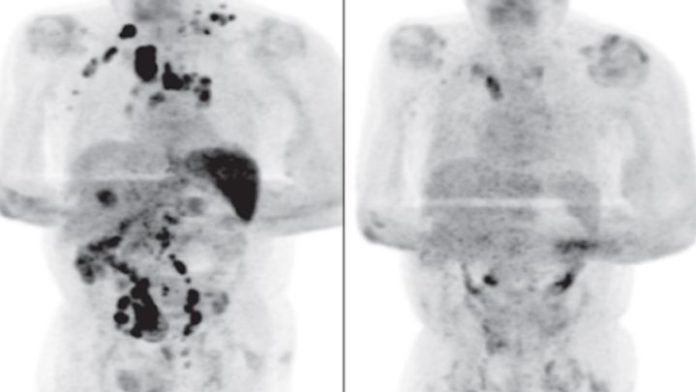

Sin embargo, volvió luego de cuatro meses para iniciar su tratamiento por el linfoma y los médicos notaron que los ganglios habían disminuido drásticamente, señalaron que el Covid-19 habría generado una respuesta antitumoral en su sistema inmune.